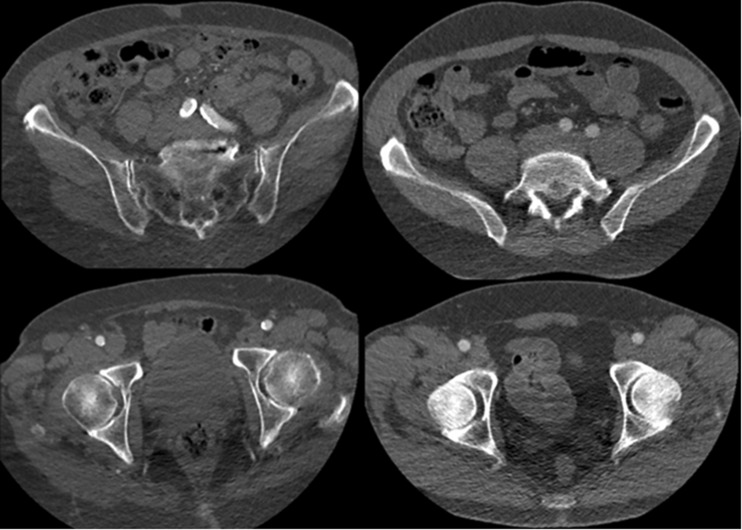

Fig. 2.

Images show the iliofemoral arteries obtained by the 80 kVp (left) and the 70 kVp (right) high-pitch CTA